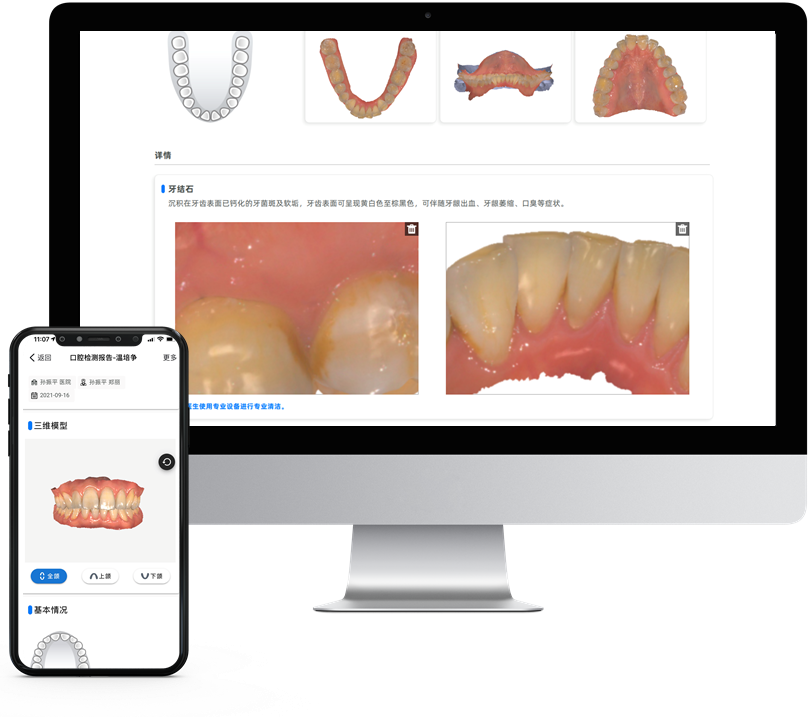

口腔健康檢查3D報告

了解更多,參與更多,滿意更多

病例報告包括齲齒、牙缺失、牙結石、色素等

標準化接診療程,便于病例追蹤及分析

生成二維碼分享查看

*口腔健康檢查3D報告、正畸模擬、一鍵打印為附加選購模塊非標準功能配置,詳情請咨詢區域銷售。